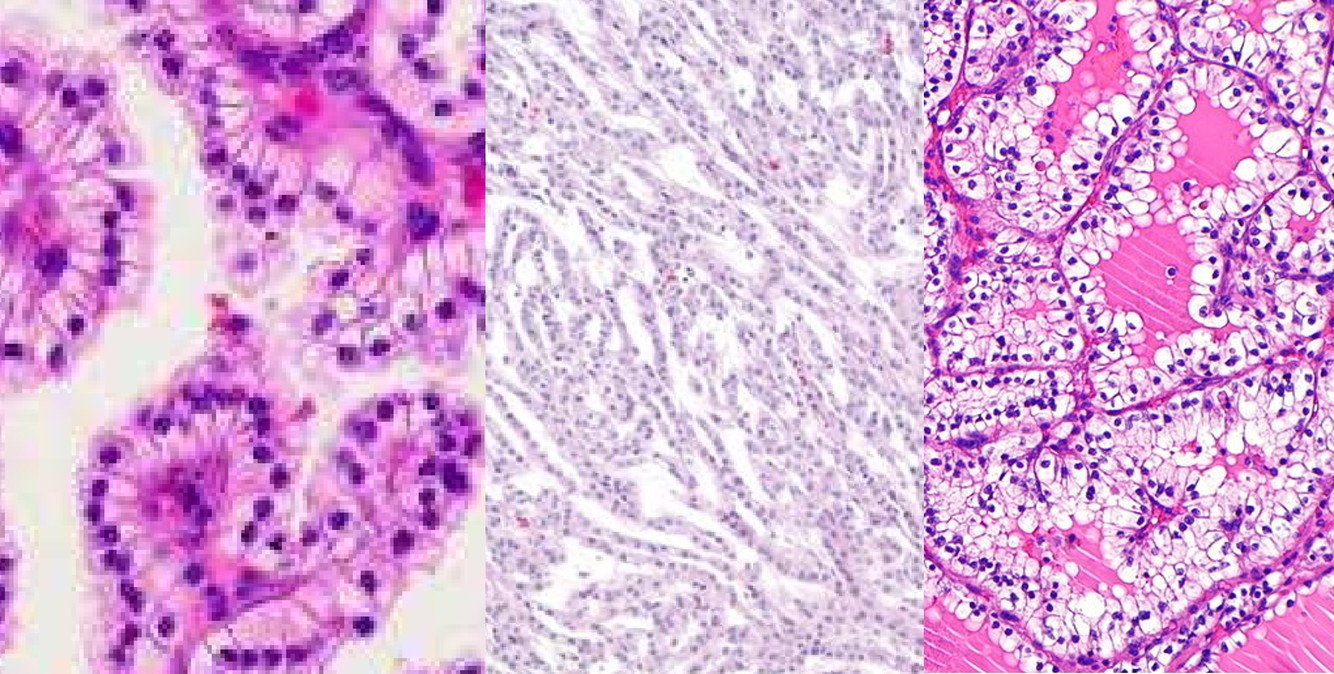

Clear Cell Papillary Renal Cell Carcinoma

- Tubular, cystic and papillary patterns

- Single layer of cuboidal cells, scant eosinophilic or moderate clear cytoplasm, subnuclear clearing

- Low grade and stage

- Positive stains:

- CK7, +/- focal CD10

- Negative stains:

- Racemase

- Sporadic, ESRD

PAPILLARY RCC

- Type 1

- small cells, clear to basophilic cytoplasm, single layer of small oval nuclei, inconspicuous nucleoli

- foamy macrophages and/or edema, psammoma bodies and calcium oxalate crystals

- low grade

- Type 2

- large cells, abundant eosinophilic cytoplasm, pseudostratified or apical large spherical nuclei, prominent nucleoli

- macrophages, edema, psammoma bodies

- high grade

- Cytogenetics: 7+, 17+, Y-

- Better prognosis than clear cell RCC

- Positive stains: CK7, Rasimase

COLLECTING DUCT CARCINOMA

- AKA Bellini duct carcinoma

- Firm mass in medulla

- Infiltrating tubular or tubulopapillary

- Desmoplastic stroma

- +/- cytoplasmic and intraluminal mucin

- High grade

- Poor prognosis

- Rule out met

- (+) E-cadherin, PAX8, L&Hmw CK (var)

- (-) AMACR, racemase, CD10, CK20